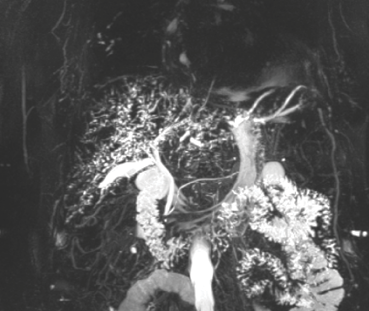

La paciente consultó nuevamente al servicio de urgencias por ictericia progresiva, se realizaron paraclínicos que reportaron alteración del perfil hepático a favor de ser colestásico (tabla 1), y ecografía de hígado y vías biliares con cambios de adenomiomatosis vesicular, descartando dilatación de la vía biliar. Se aclararon hallazgos con resonancia simple y contrastada de abdomen que evidenció patrón de colangitis esclerosante con vía biliar desestructurada de manera difusa (figuras 1 y2).

El diagnóstico de colangitis esclerosante secundaria se realiza por colangiopancrea-tografía retrógrada endoscópica (CPRE) o colangiorresonancia. Estos métodos logran identificar estenosis y dilataciones difusas de los conductos biliares intrahepáticos, y defectos de llenado con cilindros biliares [11]. En el presente caso, la resonancia simple y contrastada de abdomen evidenció el patrón de colangitis esclerosante con una vía biliar desestructurada de manera difusa, con microcálculos y barro biliar. Previo al desarrollo de estas complicaciones, la paciente tenía pruebas de función hepática con una alteración leve, y la estructura de la vía biliar era normal. Además, no tenía criterios para una colangitis esclerosante primaria, y se descartaron de manera racional otras causas secundarias.